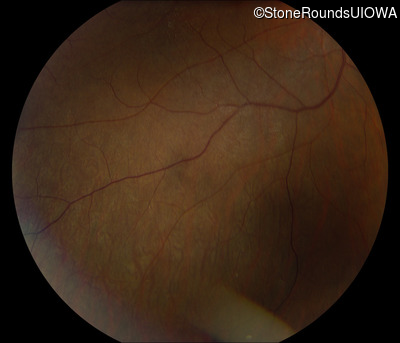

Infrared Fundus Photograph - Left - 20/50 +1

Exemplar